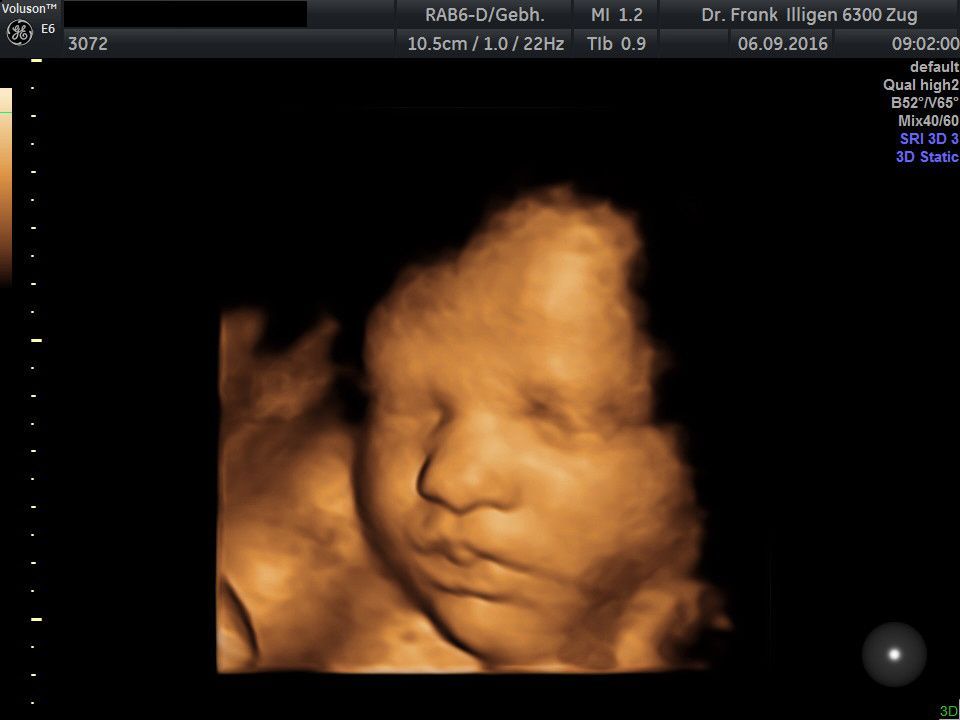

Dr. med. Frank M. Illigen

I am specialist for gynecology and obstetrics FMH, opened my medical office in Zug in 2006.

I'm attending doctor (Care during childbirth and surgery) in the Hirslanden-Klinik AndreasKlinik in Cham/Zug for all insurance classes (General, Semi-Private and Private).